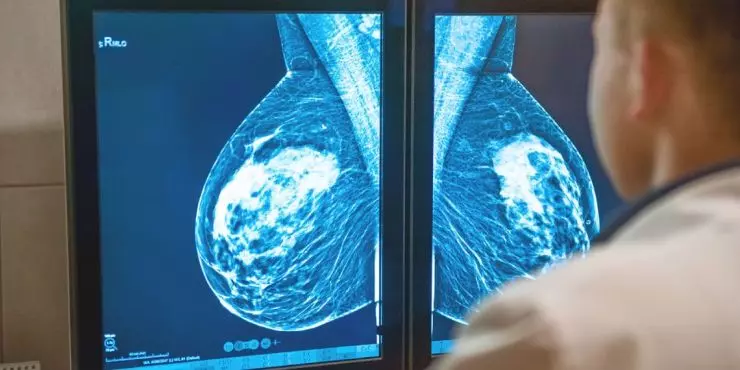

Mammograms can feel a little mysterious until you’ve had one. The short version: a mammogram is a low-dose X-ray of the breast that looks for early signs of breast cancer—often years before a lump can be felt. Early detection matters because it leads to more treatment options and better outcomes.

Digital breast tomosynthesis (3D mammogram).

Takes multiple images from different angles that a computer reconstructs into thin “slices,” which can improve cancer detection and reduce callbacks, especially in dense breasts. -

Mammograms and Breast Density

Dense breast tissue is common and can make mammograms harder to interpret. If your report mentions density, your clinician may discuss 3D mammography and whether supplemental screening (such as ultrasound or MRI based on risk) makes sense for you.